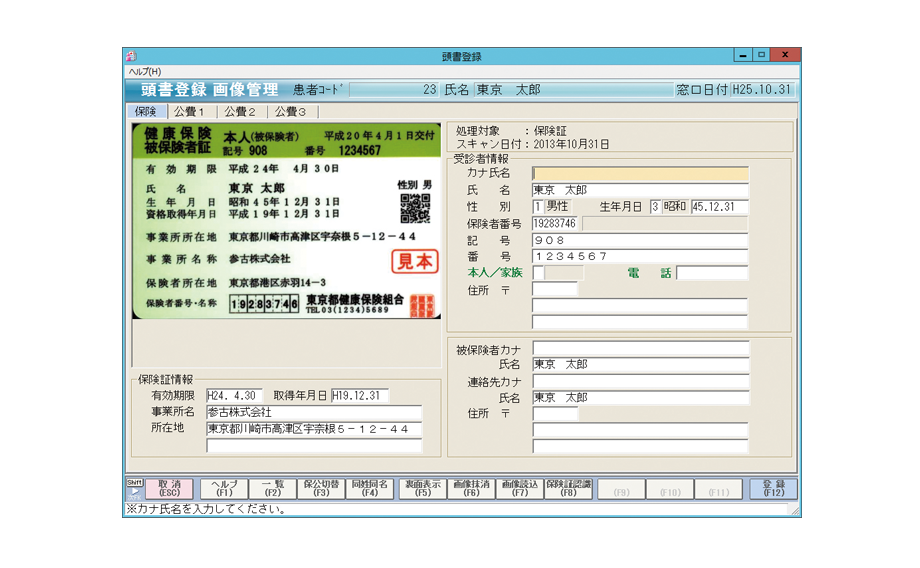

保険証認識システム

保険証の情報を自動取り込み。患者登録時の手間削減、入力ミスの防止に役立ちます。カードタイプや紙の保険証のほか、公費受給者証も取り込み可能です。情報の取り込みだけでなく、保険証や受給者証の画像を保存することもできます。